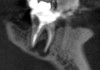

The next step in the diagnostic process was to perform objective clinical sensibility pulpal and periradicular testing to determine the etiology of the patient's chief complaint. A periapical radiograph was taken of tooth No. 18 that showed a radiolucent area present around both the mesial and distal roots(Figure 3). Tooth No. 18 tested abnormal to percussion and bite tests. Palpation, periodontal probings, and mobility were within normal limits. Tooth No. 17 had been previously extracted, and tooth No. 19 tested within normal limits to cold, percussion, palpation, bite test, mobility, and periodontal probing sensibility tests.

Preoperative periapical radiograph of tooth N o. 18.

Fig 3.